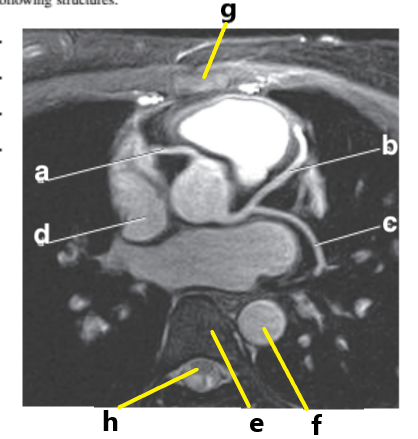

Which letter is the Pulmonary trunk ?

d

What is letter b ?

Left ventricle

Which letter is the superior vena cava ?

What is letter h ?

What is letter d ?

Right ventricle

What is letter g ?

Right atrium